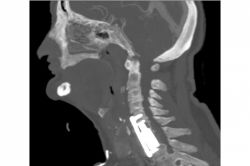

70 yaşındaki tümör hastası sağlığına kavuştu